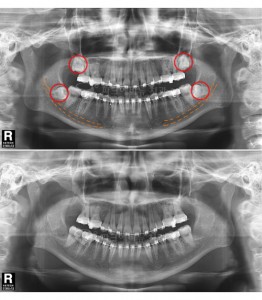

파크에비뉴치과 사랑니 발치 전 후 비교

위 두 환자는 교정치료를 위한 공간확보가 필요하여 사랑니 발치를 하게 되었다. 아래턱에 점선으로 표시 되어있는 하치조신경 다발이 사랑니 뿌리에 근접하여 지나가서 난이도가 높은 수술이었지만 3차원적 영상인 CT와 Panorama X-ray를 정밀 분석하여 발치 한 결과 신경 손상 없이 발치 할 수 있었다. 또한 두 환자 모두 “PRF(자가골성장인자)”를 이용해 사랑니 발치를 하여 부작용을 최소화 하였다.